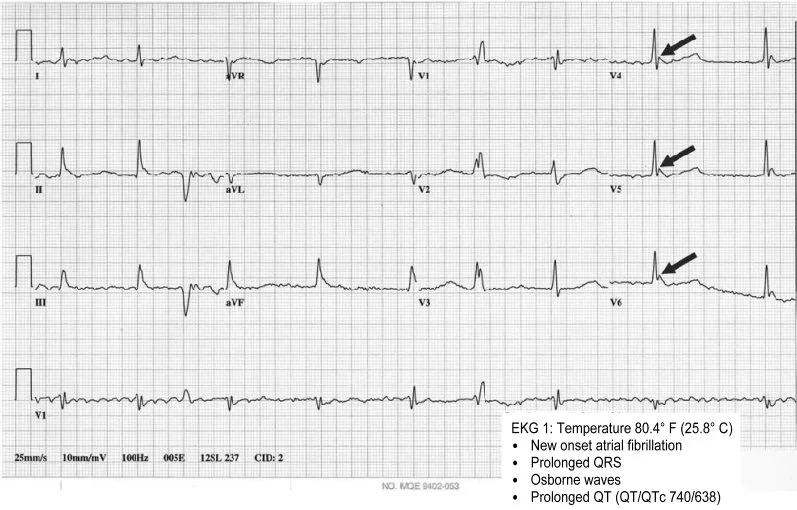

EKG changes are common with moderate to severe hypothermia and can be important assessment factors to consider. As patients become more hypothermic and their conduction overall slows, they become bradycardic. Both the QT and PR interval prolong (AHA).

Severe hypothermia (<86F/<32C) can cause a progressive widening of the QRS and risk the development of ventricular fibrillation. Take caution when moving these patients, as their already irritable hearts can be pushed into a dysrhythmia

Osborne/ J Waves

Osborne waves are a classic finding of significant hypothermia in which the J point develops a notched appearance that can resemble delta waves (Mareedu et al., 2008). These do not necessarily serve as an indicator of mortality, but they are roughly proportional to the degree of hypothermia present (Mareedu et al., 2008).

Sourced from research article. This EKG shows highlighted Osborne waves.